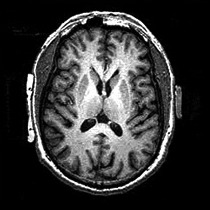

5.2 Results on smooth images

In Fig. 4, we show a comparison between C-TETRIS and CEN on the segmentation of the set of smooth images. For the sake of completeness we report also the segmentation results produced by CEN on the cartoon of the images. In general, the segmentations produced by C-TETRIS are comparable with or better than the ones produced by CEN. The segmentation of airplane shows the great effectiveness of the proposed model to separate accurately a non-uniform background from the object, due to the ability of C-TETRIS to remove the remaining texture in the cartoon, as showed in Fig. 2. We note that in general there are no significant differences in the quality of the segmentation results between CEN applied to the original image and CEN applied to the cartoon. However, in the case of ultrasound the segmentation on the cartoon produces unreliable result, due to the loss of contrast introduced by decomposition. In Table 2, two global metrics are listed to measure the contrast between the given image and its cartoon. In particular we used

original image cartoon CEN CEN on cartoon C-TETRIS

Refer to caption Refer to caption Refer to caption Refer to caption Refer to caption

airplane

squirrel

brain

ultrasound

Figure 4: Segmentations of smooth images by CEN and C-TETRIS. The results of the segmentation produced by CEN on the cartoon part of the image are also shown.